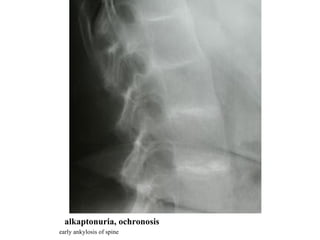

alkaptonuria, ochronosis early ankylosis of spine

alkaptonuria, ochronosis grosslycalcified intervertebal discs